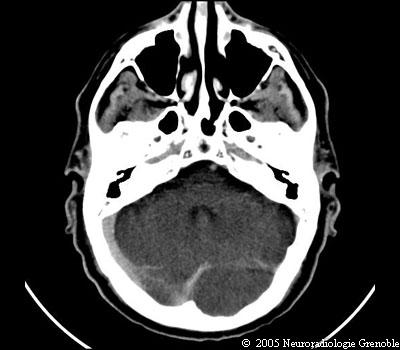

Radioanatomie TDM de l'encéphale

TDM cérébrale sans injection